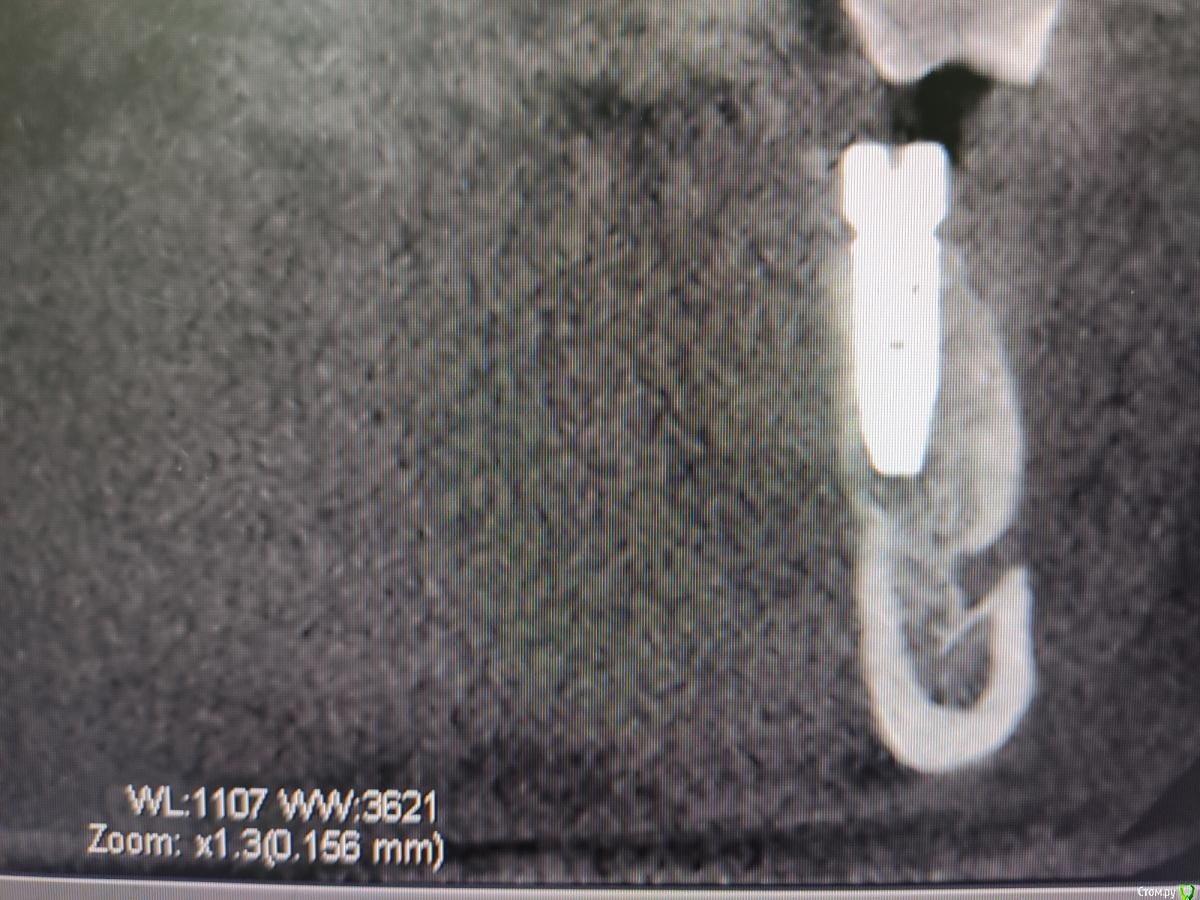

Дмитрий М Опубликовано 14 октября, 2020 Поделиться Опубликовано 14 октября, 2020 чтобы не создавать новых тем, коллеги подскажите, что за периапикальные изменения на снимке имплантация 4 мес.назад,КТ свежее, жалоб нет Ссылка на комментарий

meddikus Опубликовано 24 октября, 2020 Поделиться Опубликовано 24 октября, 2020 чтобы не создавать новых тем, коллеги подскажите, что за периапикальные изменения на снимке 1602515938806.jpg1602515938810.jpg1602515938814.jpg имплантация 4 мес.назад,КТ свежее, жалоб нет вас интересует резорбция на апексе? Ссылка на комментарий

Дмитрий М Опубликовано 25 октября, 2020 Поделиться Опубликовано 25 октября, 2020 чтобы не создавать новых тем, коллеги подскажите, что за периапикальные изменения на снимке 1602515938806.jpg1602515938810.jpg1602515938814.jpg имплантация 4 мес.назад,КТ свежее, жалоб нет вас интересует резорбция на апексе? да Ссылка на комментарий

Zolotoy255 Опубликовано 27 октября, 2020 Поделиться Опубликовано 27 октября, 2020 Переимплантит и выкручивать?очень похоже на "перирентгенит" , сделайте прицел в перпендикулярной проекции + ждите до формика. КТ аппараты в зависимости от настроек отдельно взятого могут светить по разному отсюда типо "пустоты". Просто ждите RG контроль 1 мес, 3 мес, на этапе формика поймете когда откроете. Думаю истин не открыл но дома скучно. Ссылка на комментарий

Zolotoy255 Опубликовано 27 октября, 2020 Поделиться Опубликовано 27 октября, 2020 чтобы не создавать новых тем, коллеги подскажите, что за периапикальные изменения на снимке 1602515938806.jpg1602515938810.jpg1602515938814.jpg имплантация 4 мес.назад,КТ свежее, жалоб нетТут КТ бы покрутить в живую. Тяжело сказать однозначно , на нижнем фото похож на воспалительный генез хронического течения (НО это только похож) Как на самом деле.... нужно разбираться . По 3м фоткам это как со стаканом на половину заполненным водой (кому-то полу пустой , кому-то полу полный). Но что-то мне подсказывает что может найтись спец по чтению подобных случаев и выставлению диагноза с вероятностью в 99.9 % Ссылка на комментарий

Дмитрий М Опубликовано 28 октября, 2020 Поделиться Опубликовано 28 октября, 2020 Тут КТ бы покрутить в живую. Тяжело сказать однозначно , на нижнем фото похож на воспалительный генез хронического течения (НО это только похож) Как на самом деле.... нужно разбираться . По 3м фоткам это как со стаканом на половину заполненным водой (кому-то полу пустой , кому-то полу полный). Но что-то мне подсказывает что может найтись спец по чтению подобных случаев и выставлению диагноза с вероятностью в 99.9 % буду наблюдать в динамике, контрольный снимок через 2 мес,сам больше склоняюсь, что это что-то вроде фиброзной капсулы вокруг апекса импланта Ссылка на комментарий

Nazim_NV86 Опубликовано 29 октября, 2020 Поделиться Опубликовано 29 октября, 2020 что-то вроде фиброзной капсулы вокруг апекса импланта Кость там плотная. Мелкая пыль и асептический некроз. Инкапсуляция. Очень давно встречал такую картину. Тогда помню решил для себя так... Вариант Б. Переснять на RVG. И непонятно какое сечение показывает верхний аксиальный срез. 1 Ссылка на комментарий

Дмитрий М Опубликовано 29 октября, 2020 Поделиться Опубликовано 29 октября, 2020 Кость там плотная. Мелкая пыль и асептический некроз. Инкапсуляция. Очень давно встречал такую картину. Тогда помню решил для себя так... Вариант Б. Переснять на RVG. И непонятно какое сечение показывает верхний аксиальный срез. перед протезированием проверим на ой-тест и сделаем визио Ссылка на комментарий